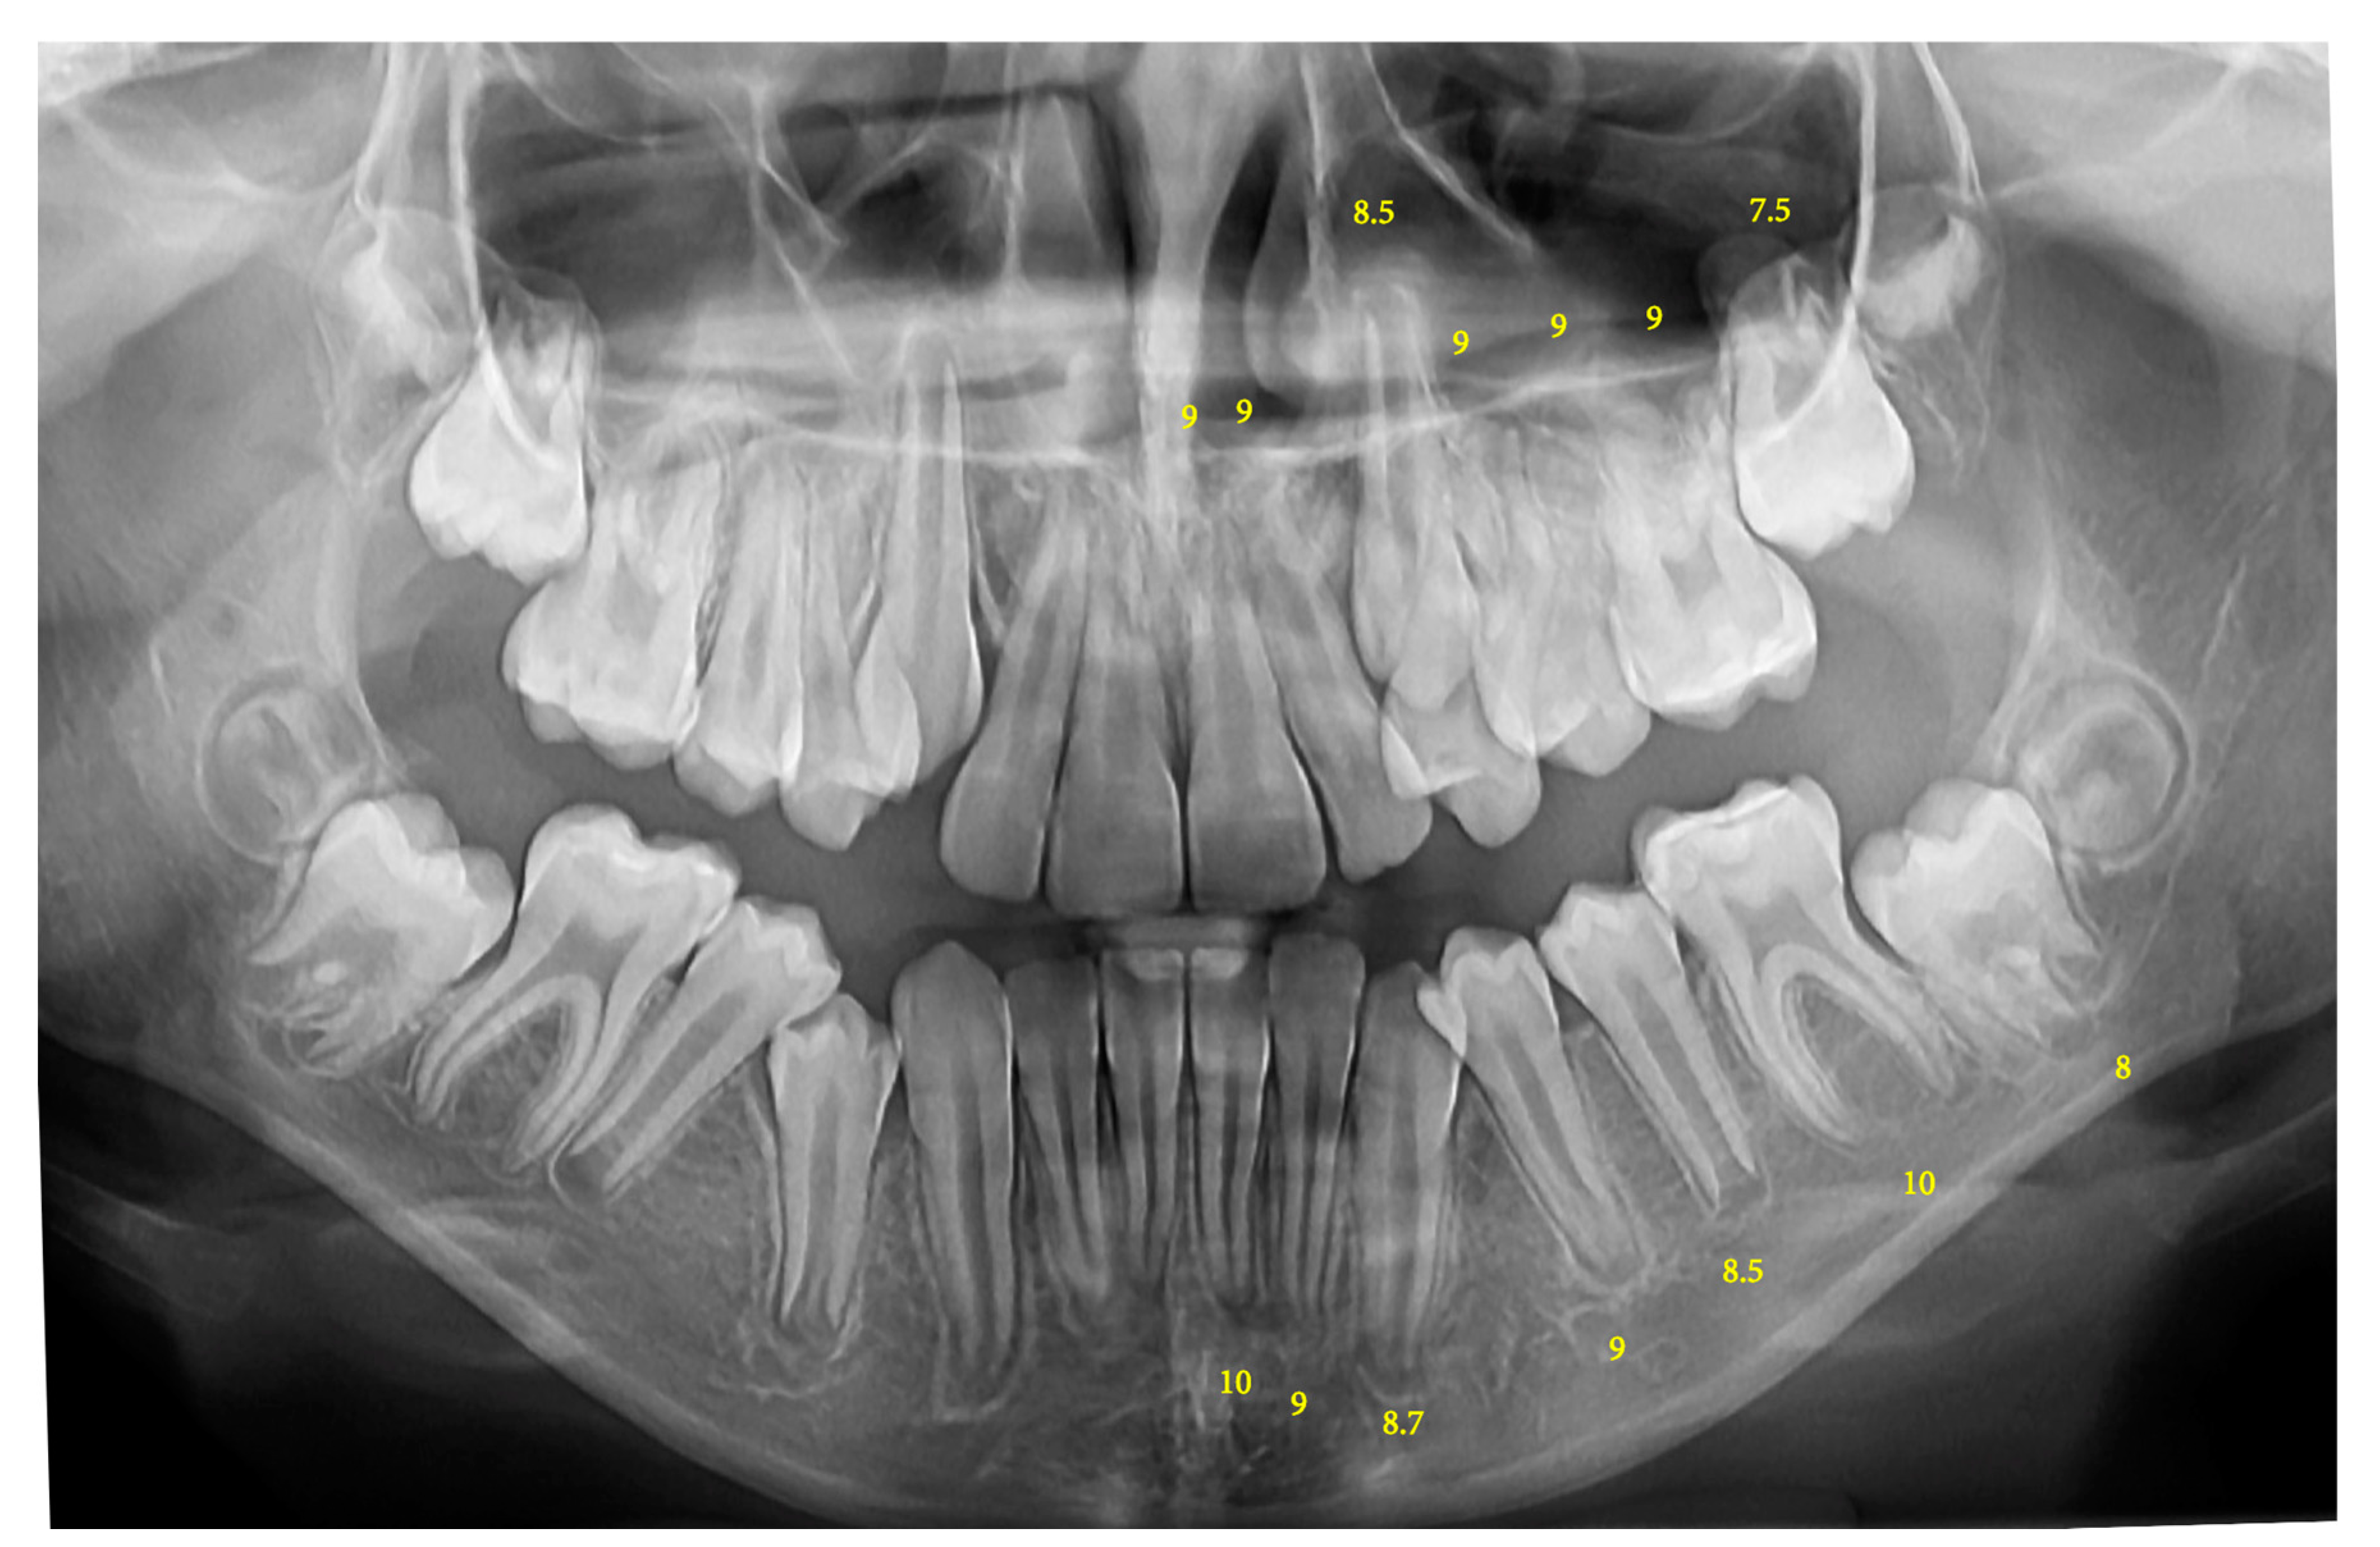

| 8–8.9 years | 8.42 | 0.26 | 7.21 | 0.69 |

| 9–9.9 years | 9.46 | 0.31 | 7.98 | 0.78 |

| 10–10.9 years | 10.37 | 0.26 | 8.71 | 0.79 |

| 11–11.9 years | 11.43 | 0.29 | 9.54 | 1.01 |

| 12–12.9 years | 12.41 | 0.30 | 10.2 | 0.90 |

| 13–13.9 years | 13.37 | 0.30 | 11.43 | 0.87 |

| 14–14.9 years | 14.45 | 0.29 | 11.85 | 1.07 |